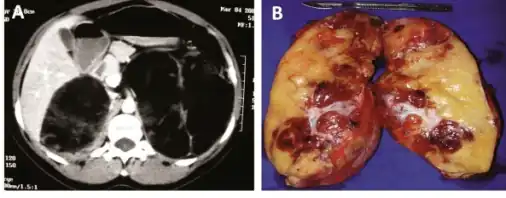

Macroscopic features

Myelolipomas are usually found to occur alone in one adrenal gland, but not both. They can vary widely in size, from as small as a few millimetres to as large as 34 centimeters in diameter. The cut surface has colours varying from yellow to red to mahogany brown, depending on the distribution of fat, blood, and blood-forming cells. The cut surface of larger myelolipomas may contain haemorrhage or infarction.[1]

The cut surface shows colour variegation from yellow to red to brown depending on the distribution of fat, blood and myeloid elements

a)CT scan showing heterogeneous bilateral myelolipomas b) macroscopic aspect of left adrenal myelolipomas